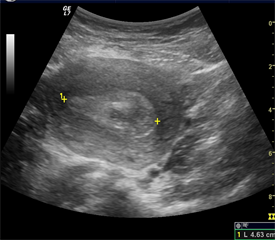

As ultrasonography findings, threatened abortion (29.8%) was the commonest cause of first trimester vaginal bleeding. This similar trend was observed in other studies [2] [3] [4] [7] [8] . Threatened abortion is the result of marginal abruption with separation of the chorion from the endometrial lining and subchorionic hemorrhage which can lead to an abortion. On ultrasonography, subchorionic hemorrhage (Figure 1) is either hypoechoic or echoic depending on the age of the blood products at the time of the US examination [4] .

Figure 1. USG shows a massive subchorionic hemorrhage (calipers) surrounding the gestational sac.